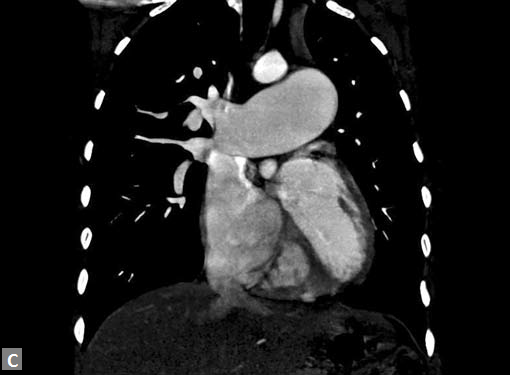

Right ventricular strain is picked up when RV/LV ratio is

more than one with deviation of interventricular septum to

left.